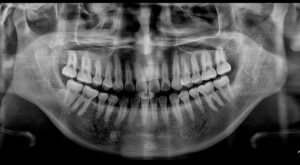

잔여 뿌리 없이

깔끔하게 발치가 마무리된

파노라마 사진입니다.

환자분께서는 사랑니 발치에 대해

걱정이 많으셨는데

생각보다 어렵지 않게 발치를 진행할 수 있어

만족해하셨습니다.